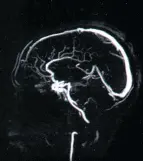

ПРИМЕРЫ ИЗОБРАЖЕНИЙ, сделанных на нашем оборудовании.

Исследование головного, спинного мозга и сосудов. Уникальные возможности оборудования позволяют визуализировать сосуды головного мозга и с высочайшей степенью достоверности, диагностировать сосудистую патологию головного мозга, включая сосудистые программы для оценки состояния мелких сосудов.